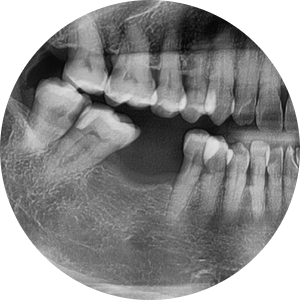

Initial X-ray at the first visit

She visited us saying, “The molar space where I had a tooth extracted before has been bothering me more lately, and I can’t chew food well.”

A foreign woman in her 50s came to the clinic,

and the panoramic X-ray showed that the first molar on the lower right had been left in an extracted state, with the adjacent teeth beginning to tilt slightly.